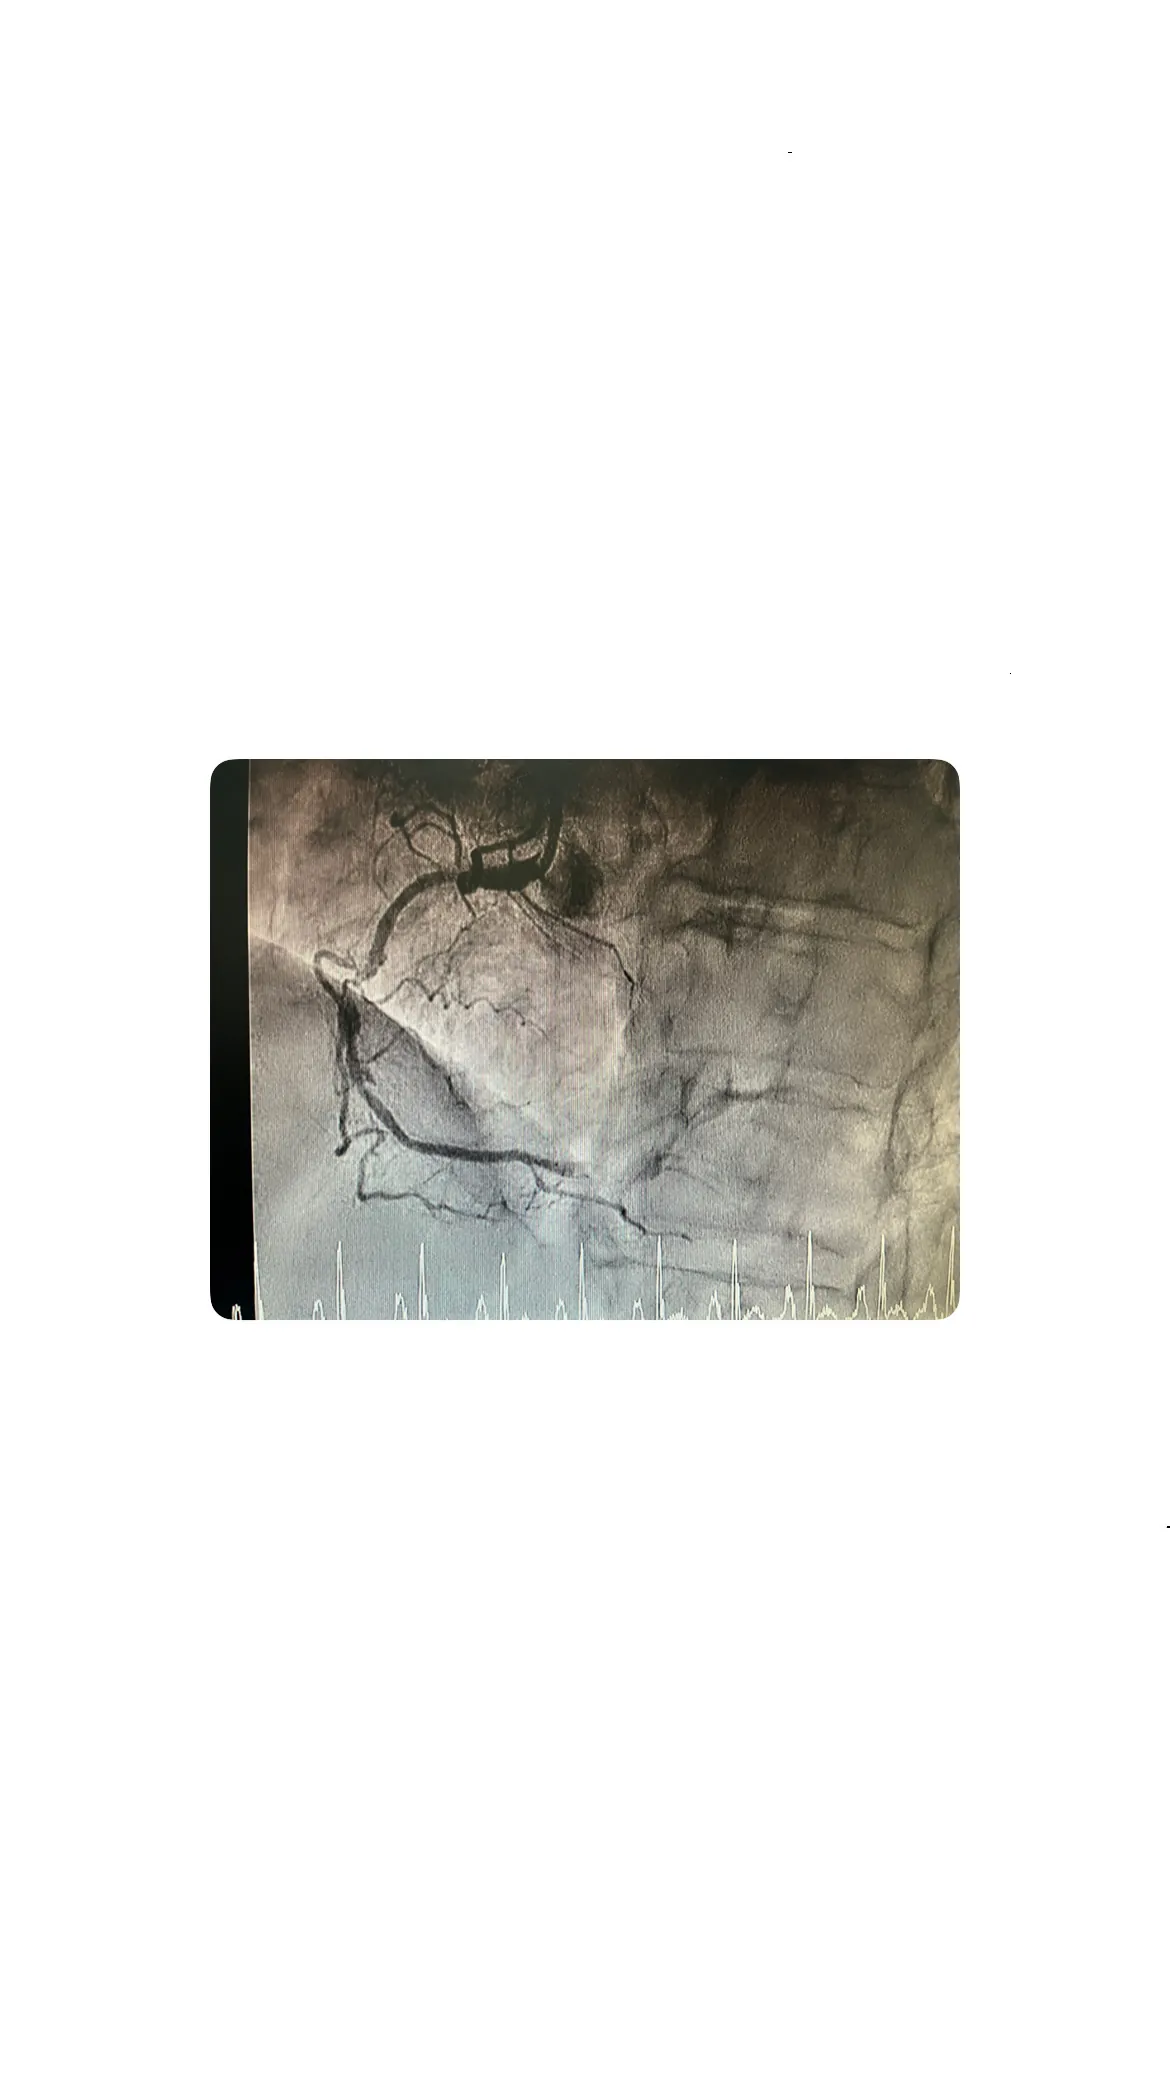

Cateterismo por radial derecha: técnica y hallazgos

El cateterismo se realizó a través de la arteria radial derecha, una técnica menos invasiva que permite una recuperación más rápida.

Enfermedad de la descendente anterior y coronaria derecha

Se identificó enfermedad en la arteria descendente anterior y una lesión a nivel medio en la coronaria derecha, junto con una oclusión crónica distal. Estos hallazgos complican la situación, requiriendo un enfoque integral para la revascularización.